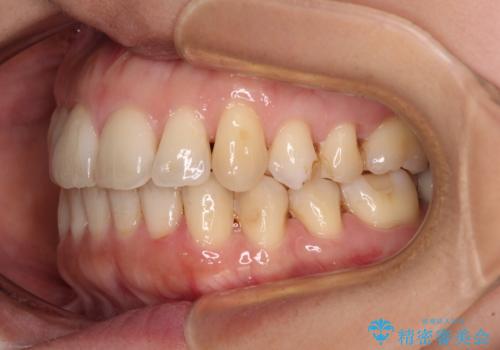

- 上下奥歯の欠損を気にして来院された患者様です。

以前矯正した後戻りにより前歯に叢生が認められたため、矯正治療の提案をしたところ、補綴治療と合わせて矯正治療を行うこととしました。

後戻りの程度は軽度であったため、インビザライン・ライトを用いて歯列を整えました。